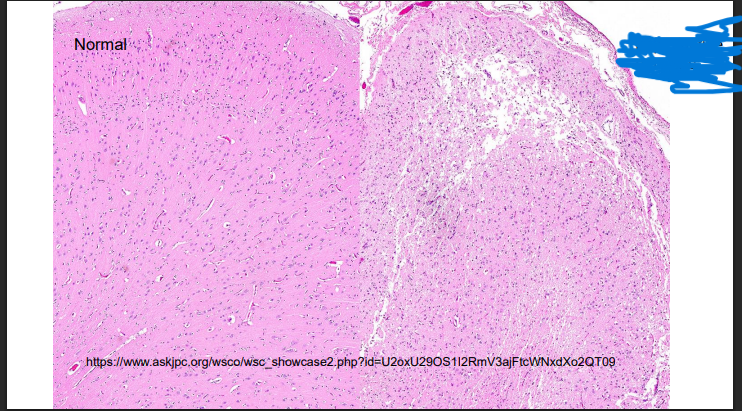

What can you see and give a possible cause

Chronic abscess of the vertebrae

Liquefactive necrosis

cause – Arcanobacerterium pyogenes